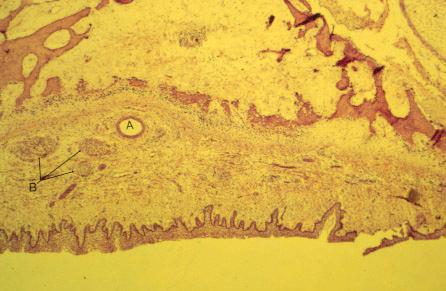

K-slide 30: Still higher magnification of slide 28

A. Anterior palatine artery

B. Branches of anterior palatine nerve in submucosa of hard palate